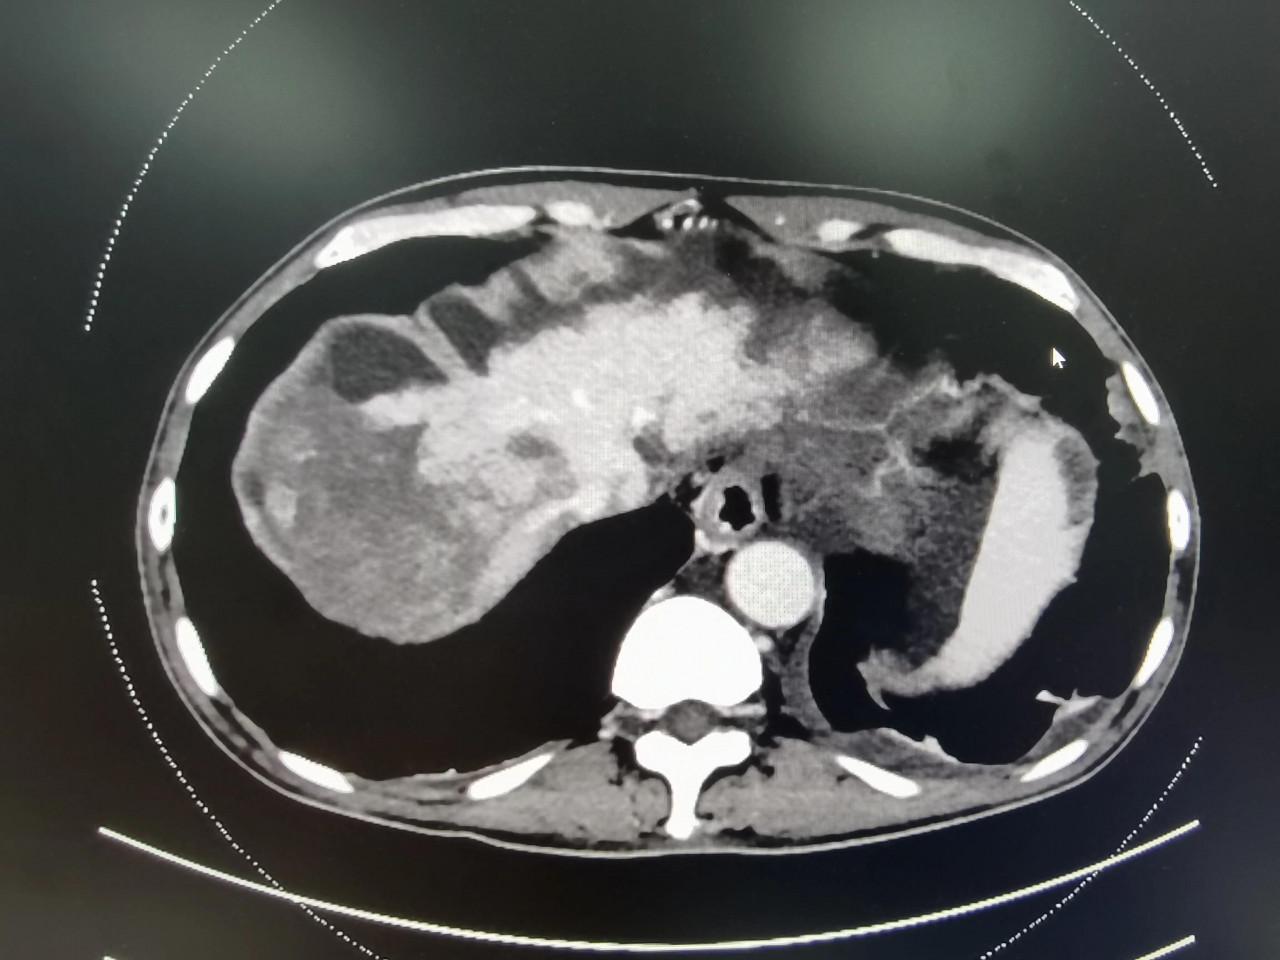

晚期肝癌的病人也不要輕易放棄!近2-3年,晚期肝癌的治療獲得了較大的突破,介入治療+靶向藥+PD1的治療組合,大部分情況下可以取得不錯的治療效果。這是一例非常晚期的肝癌病人,這要是在2-3年前,估計就是勸病人回家,該吃吃該喝喝,預計不會超過3個月的生存期。本例患者巨塊型肝癌合併下腔靜脈癌栓(下腔靜脈幾乎完全堵塞並臨近心房口了)及門靜脈主幹及右支癌栓的病人,經過2次的介入治療(肝動脈灌注化療術(HAIC)後,病灶明顯的縮小,癌栓明顯的消退,腫瘤指標直線下降,整個人的精神狀態持續好轉,未來可期。